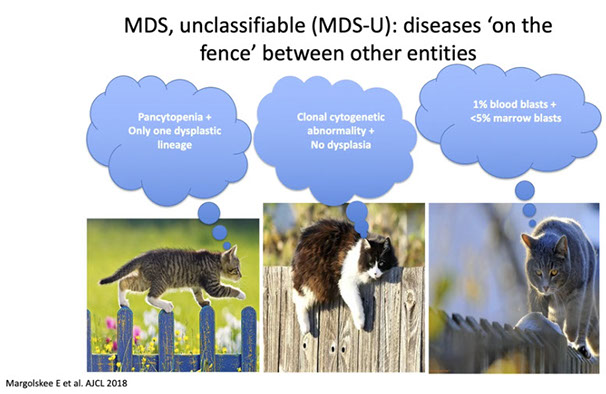

Myelodysplastic Syndromes

MDS does not progress to MPN, and MPN does not progress to MDS; evolution depends on what the original diagnosis was

Primary, neoplastic, clonal pluripotent stem cell disorders; karyotype often normal or has abnormalities seen in MDS

- One or more cytopenias in blood (ineffective hematopoiesis)

- Maturation abnormalities in bone marrow (dysplasia/dyspoiesis)

- Progressive cytopenias and BM failure c potential evolution to acute leukemias, previously known as “preleukemias”

Uni-/bicytopenia c UNI-lineage dysplasia --> RCUD (RA/RN/RT)

" " BI-lineage dysplasia (or more; +/- ringed sideroblasts) --> RCMD

Pancytopenia c UNI-lineage dysplasia --> MDS-U

MDS with single lineage dysplasia

Dysplasia and cytopenia in 1 of the 3 cell lines, including: Refractory Anemia (RA), Refractory Neutropenia (RN), and Refractory Thrombocytopenia (RT)

- can have cytopenia in 2 cell lines, but can only have dysplasia in 1

-- Pancytopenia c 1 cell line dysplasia termed MDS-U